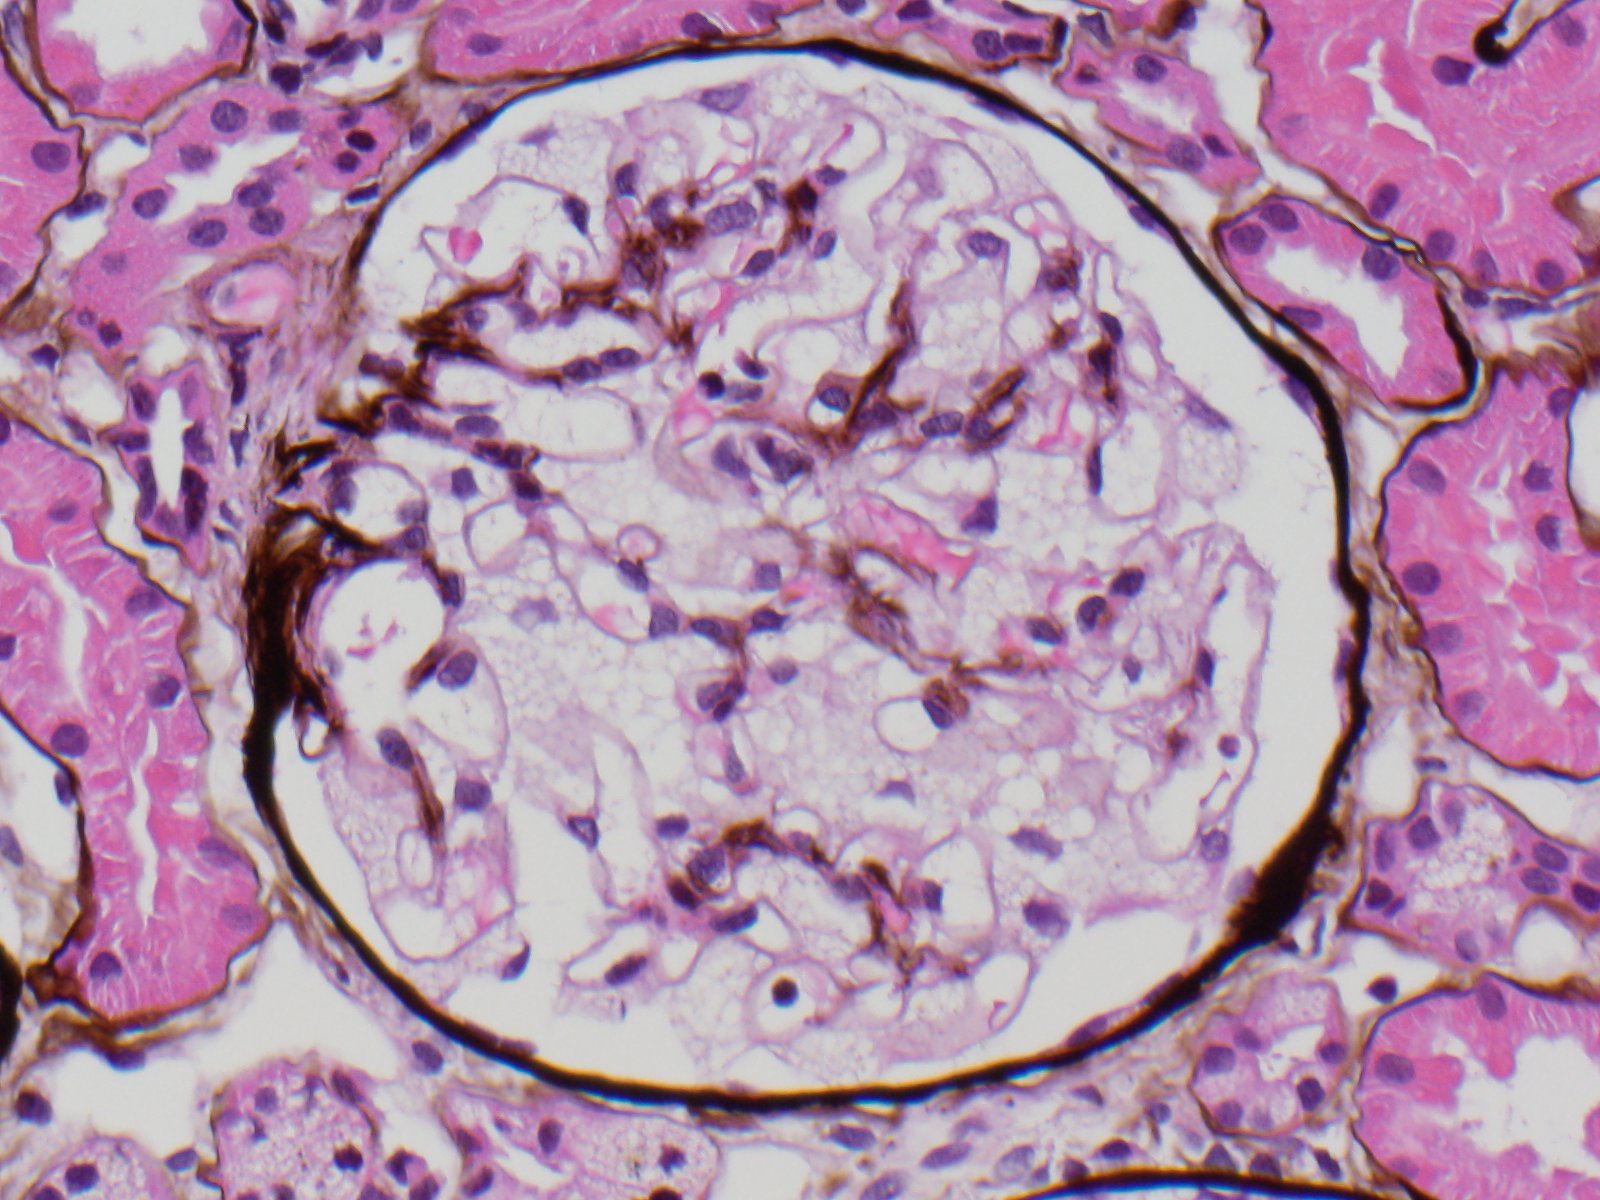

Fig B67 yo F h/o breast ca., HTN, DM II w/ 3+ proteinuria. C3 low. UIFE w/ 1 IgG K & 1 free K. FLC...

Jones2c silver stain400x19 yo F w/ fam. h/o cardiomyopathy, arrhythmia & renal dz. Cr 0.8, BUN 11. UA neg. Renal bx.

What's...